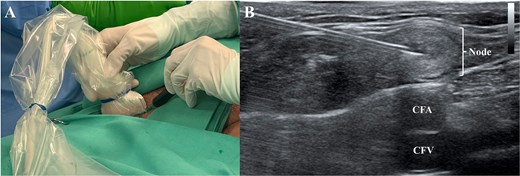

Under general anesthesia, re-exploration of the cervical site was carried out (Fig. 4). At the same time, under ultrasound guidance [8], a right inguinal lymphnode [8] was punctured with a 21G needle (Fig. 5) and the ICG was administered (0.2 mg/kg, 15 mg total) [9]. After 40 minutes, using a near-infrared camera (Hopkins® 0° NIR/ICG Optic, Storz. Tuttlingen, Germany; Fig. 6), a green bright structure was visualized. Direct and precise exploration of the lymphatic structure was carried out and the CL was identified and ligated (Fig. 7). After confirming no other CLs, the wound was closed leaving an aspirative drainage.

At the same time the cervical reexploration was being performed, the right inguinal area was prepared and under ultrasonographic guidance (A) using a 21G needle, an inguinal lymph node (B) was punctured and the indocyanine green was administered (0.2 mg/kg). CFA: Common femoral artery; CFV: Common femoral vein.